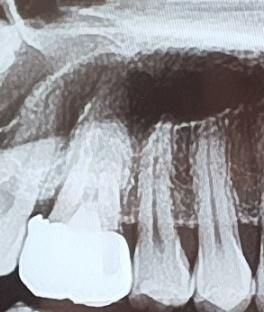

양쪽 어금니 임플란트 해야하는데 사진만으론 뼈이식을 해야하는지 알 수 없나요?

뼈이식하면 치료기간을 최소 6개월은 잡아야 할까요?

• 1번 째 사진

저정도 상태라면 뼈이식이 필요하진 않을것같고 뼈이식을 하더라도 식립하면서 뼈이식을 조금하면될것같습니다.

1. 네 섣불리 저거만 보고 판단하기엔 좀 그렇고, ct를 찍던가 아니면 수술하면서 직접 보고 판단합니다

2. 뼈이식 없이 했을때보다 조금 더 기간이 추가되긴 합니다만 기간이 얼마나 걸린다 단정지을 수 없습니다.

뼈이식을 많이 하지는 않고 조금 하면 될 것 같습니다. 6개월 정도면, 마무리될 듯 합니다.